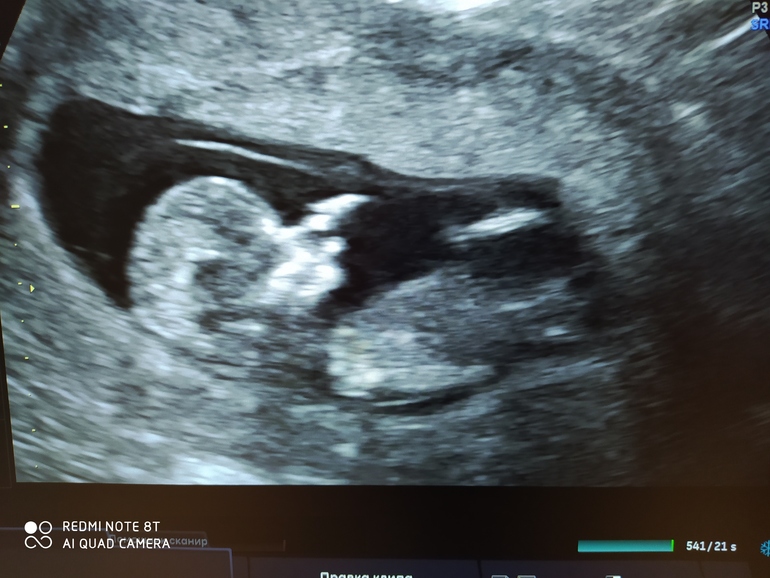

Пол малышаМногие смотрят по УЗИ и мне стало интересно. Я если честно ничего не могу здесь разобрать)

Кто у нас в домике? Мальчик третий или девчуля?

Фото только такое. Вообще удивилась, что показали и сфоткать с экрана дали.